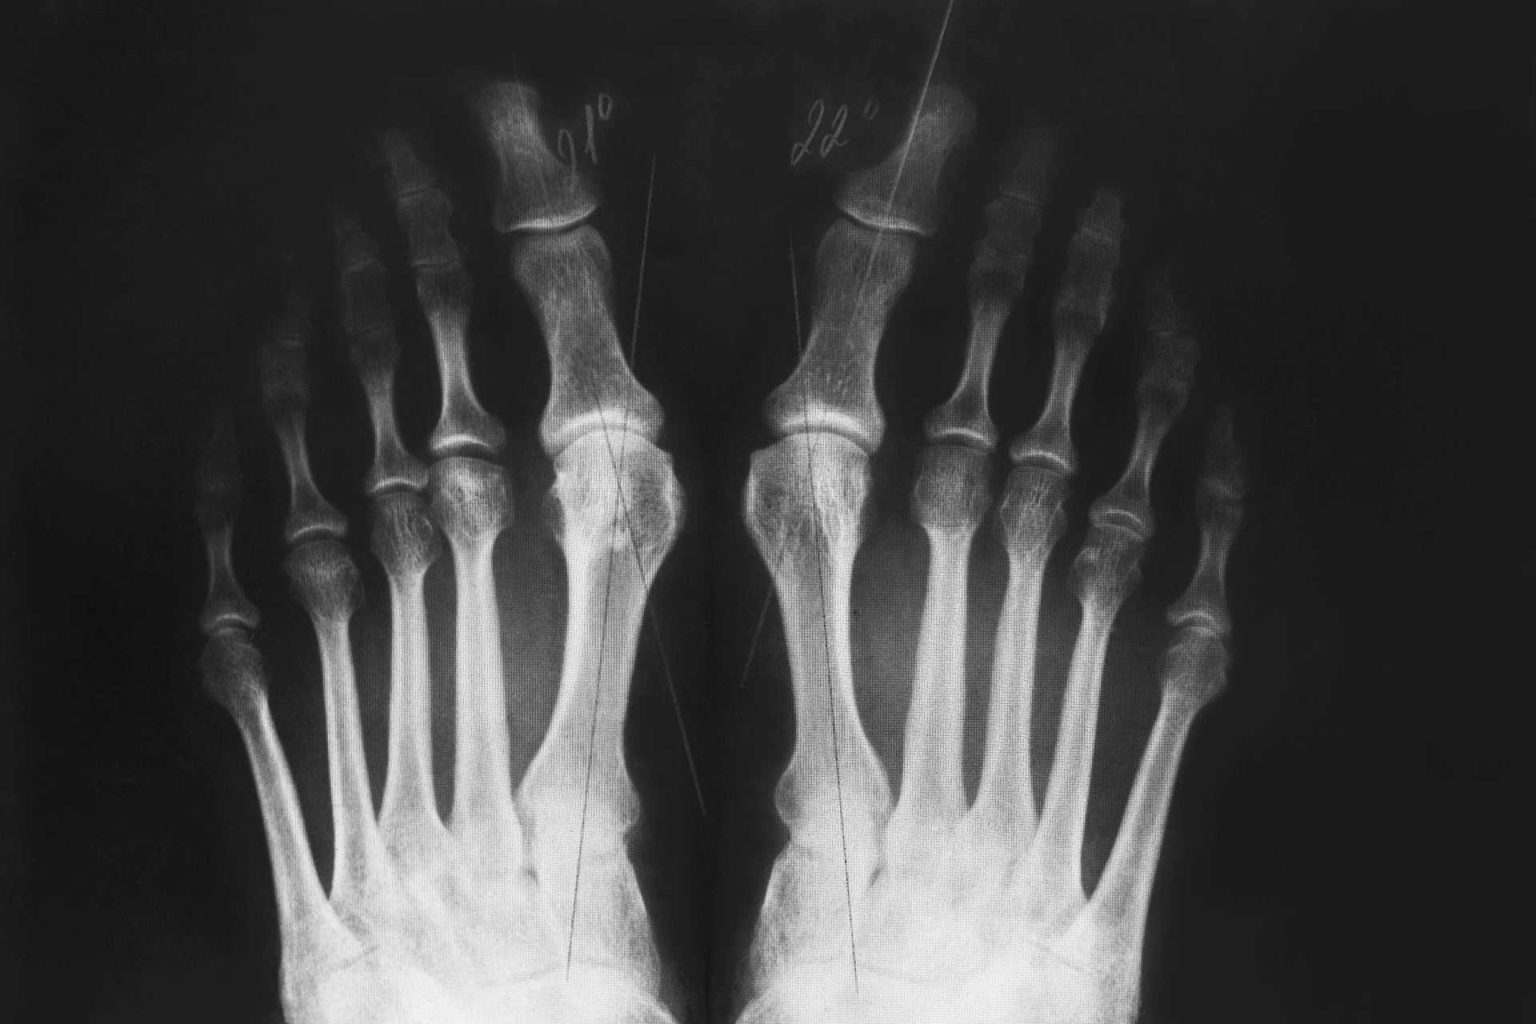

Can You Get Surgery To Straighten Your Toes . This procedure is performed to straighten the joint or joints of the toe. hammertoe surgery is a procedure to correct a deformity in the second, third, or fourth toe—a bend at the middle joint that makes the toe look like a. a hammer toe is a contracture or bent deformity of one or more joints of the toes. what is toe fusion surgery? Another surgery for individuals with a flexible hammer toe, this involves transferring tendons from the. if the joint is still flexible, it may be possible to redirect existing tendons to help straighten the toe and relieve pain. the rerouted tendons can then help straighten the toe. a hammer toe is a potentially painful deformity of the second, third, or fourth toes, where the toe bends upward at the joint,. In more severe hammer toe cases where the toe. If you are suffering from big toe. It can occur in all toes, but most commonly develops in the smaller toes. If your hammer toe has become fixed or stiff, the surgeon has two options: